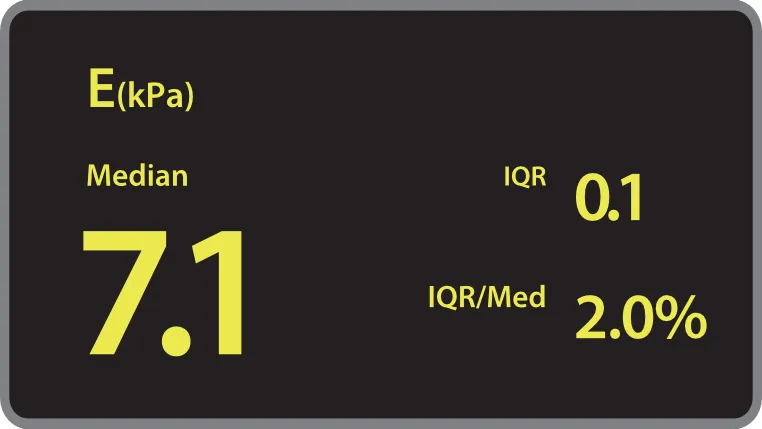

Количественный анализ ригидности печени Обеспечивает количественное определение жесткости печени и стадии фиброза печени с помощью технологии переходной эластографии

Количественный анализ ригидности печени Обеспечивает количественное определение жесткости печени и стадии фиброза печени с помощью технологии переходной эластографии Количественный анализ стеатоза печени Количественная оцененка тяжести стеатоза печени с помощью технологии LiSA (поглощения ультразвука в печени).

Количественный анализ стеатоза печени Количественная оцененка тяжести стеатоза печени с помощью технологии LiSA (поглощения ультразвука в печени).